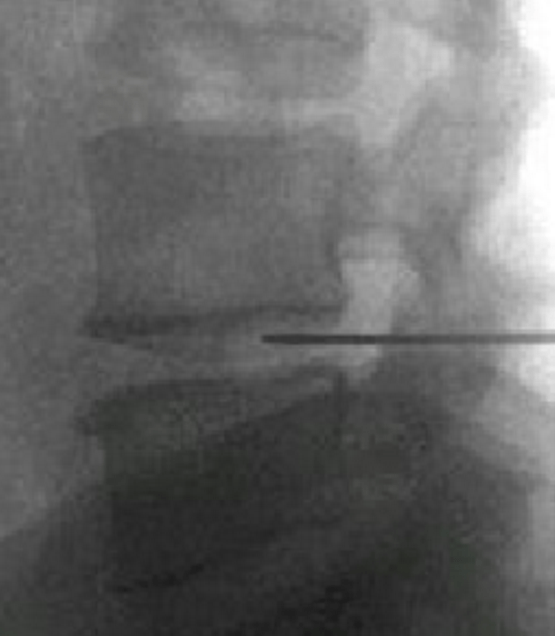

頸、腰椎間盤射頻微創(chuàng)手術(shù)

經(jīng)過多年的發(fā)展,現(xiàn)在的延安大學(xué)咸陽醫(yī)院疼痛科在診療技術(shù)上已經(jīng)達(dá)到一流的水平。尤其在頸、腰椎間盤突出微創(chuàng)治療方面,手術(shù)量居地區(qū)前列,脊柱壓縮骨折椎體成型術(shù)、頸、腰交感神經(jīng)射頻調(diào)控微創(chuàng)手術(shù)、三叉神經(jīng)痛、帶狀皰疹后神經(jīng)痛以及外周血管介入、腫瘤微創(chuàng)介入、內(nèi)臟出血等介入治療方面,為地區(qū)最優(yōu)秀的疼痛科之一。